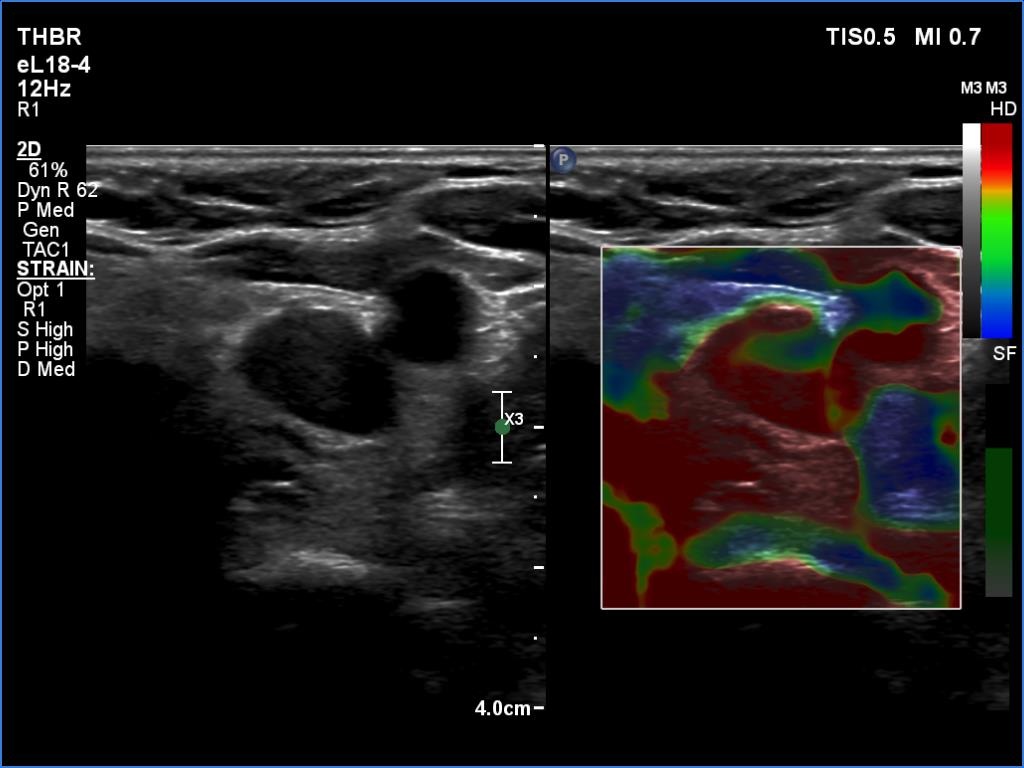

Elastography - case 650 (ultrasonographic picture 13)

Right lobe, longitudinal scan